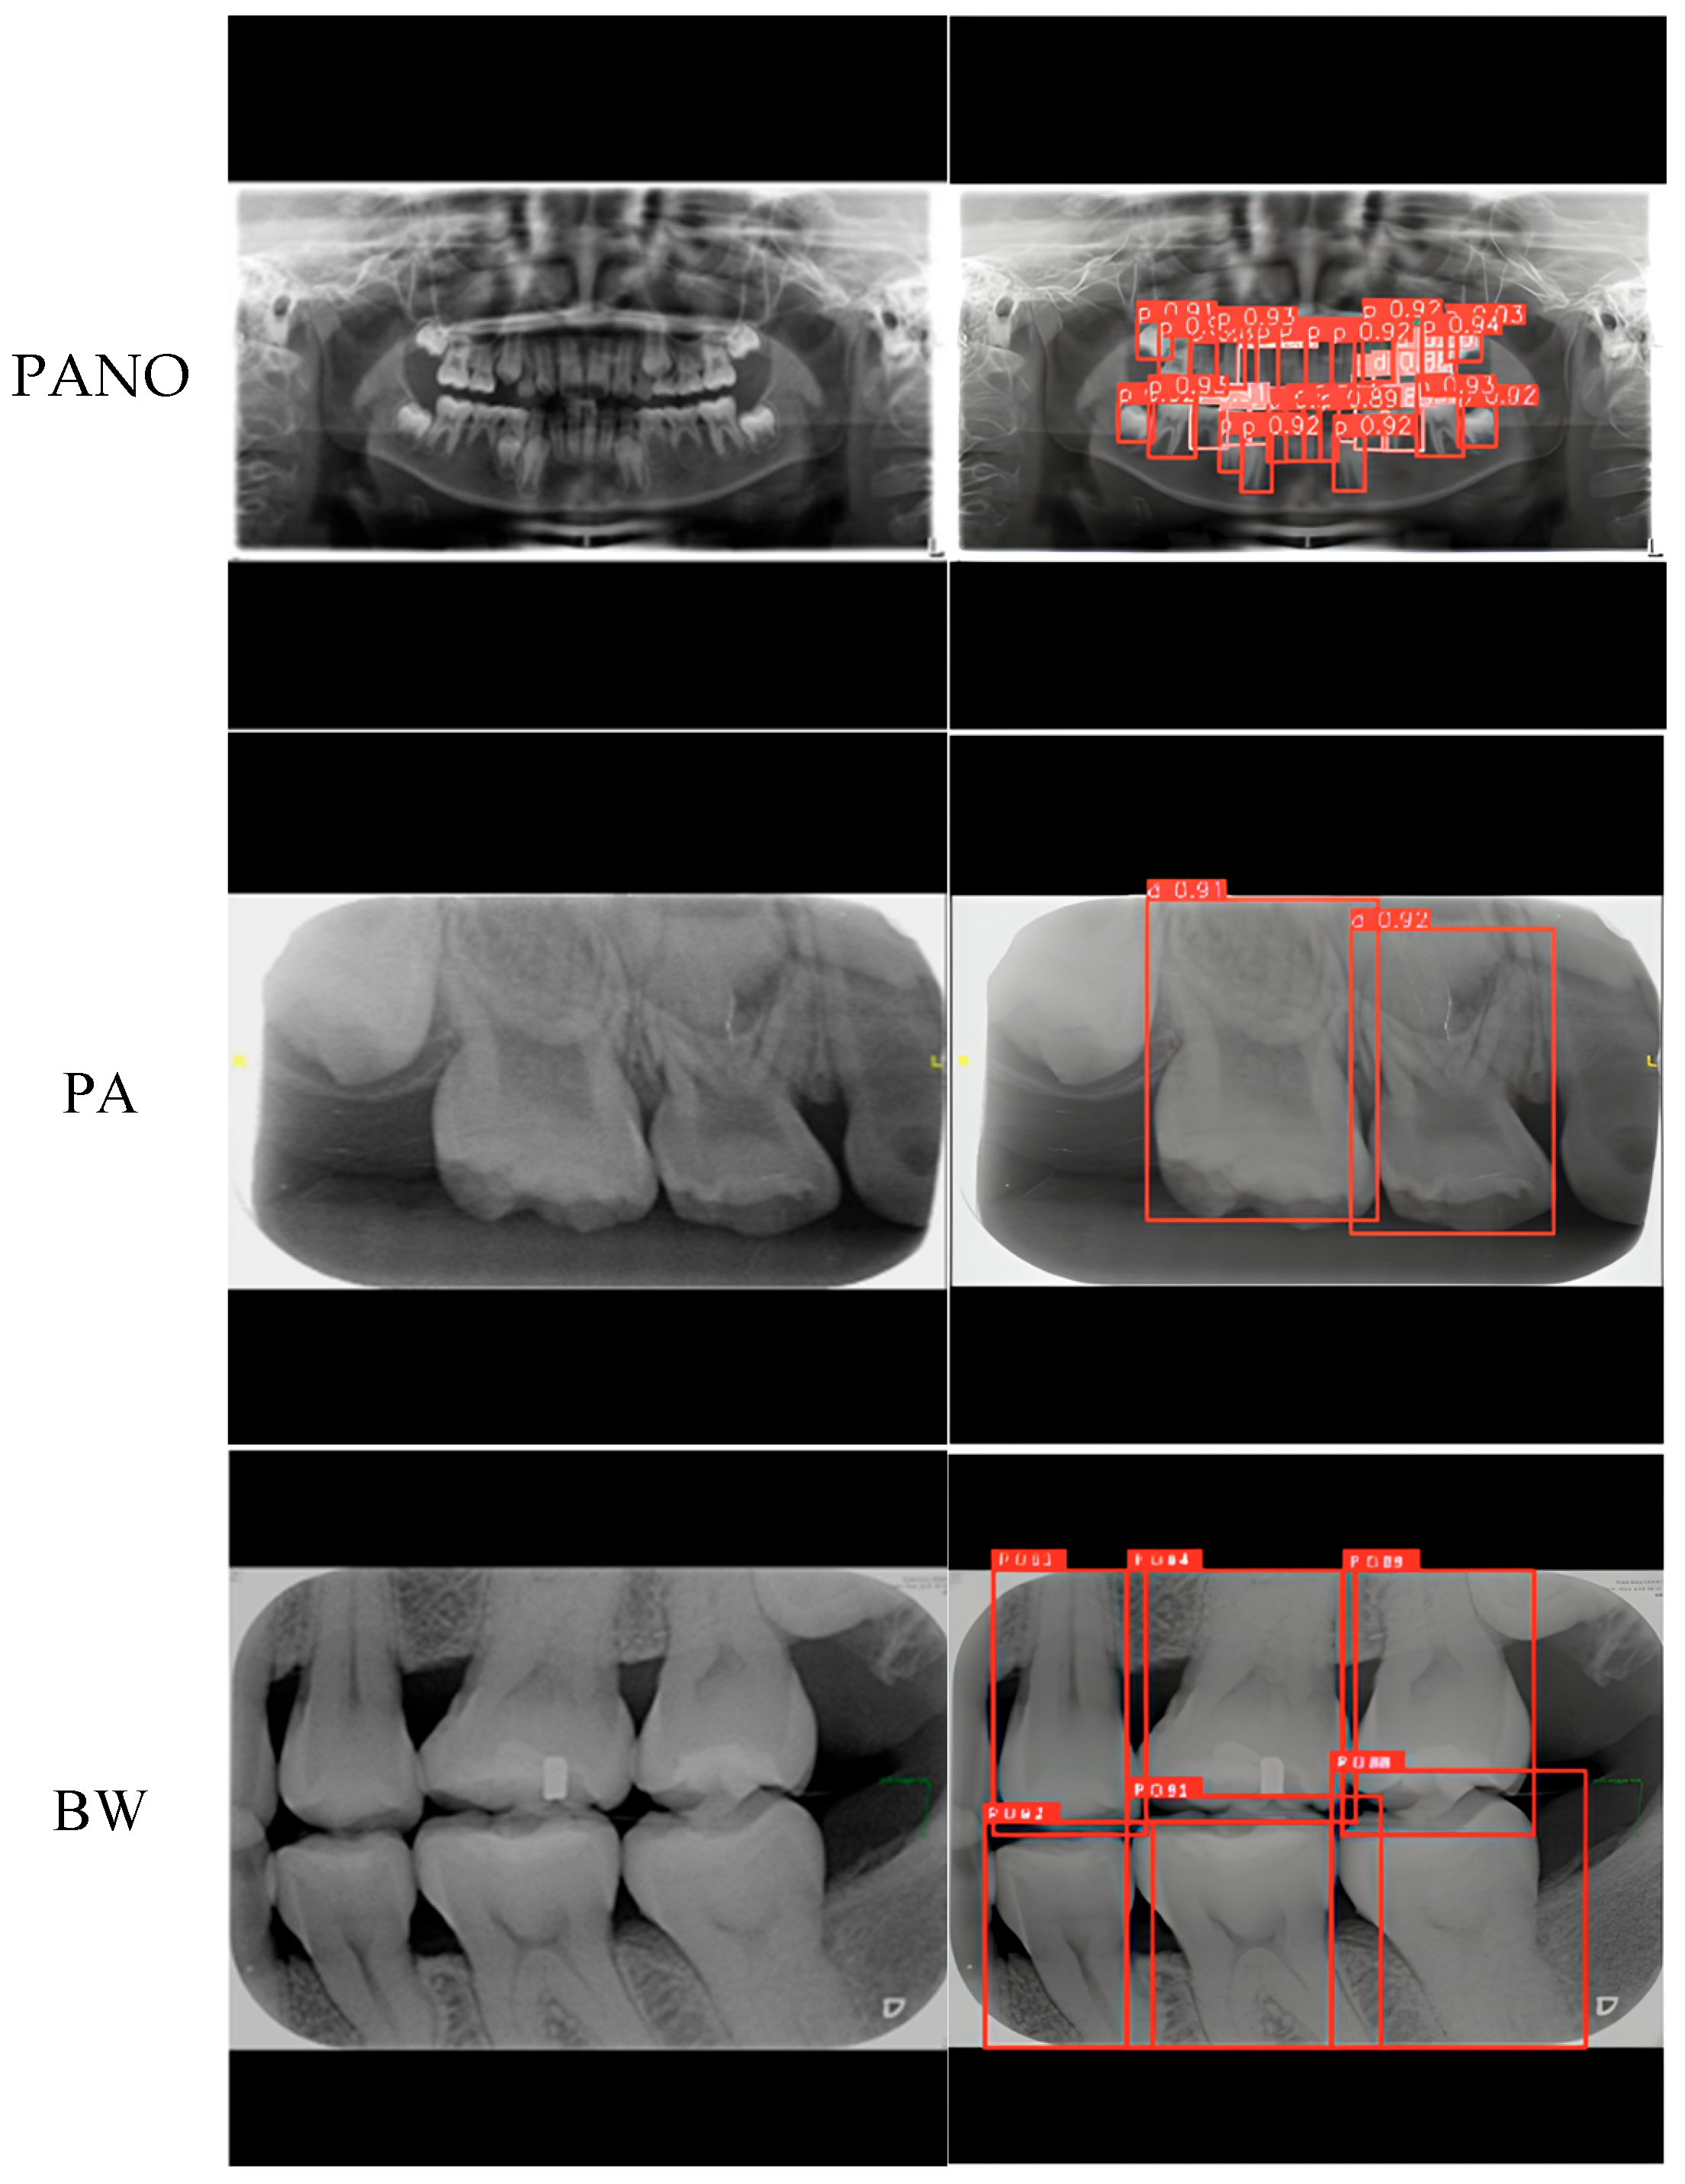

| PANO | Precision ↑ | 95.90% | 89.69% | 97.01% | 93.13% |

| Recall ↑ | 98.65% | 94.27% | 99.22% | 96.50% | |

| PA | Precision ↑ | 79.44% | 83.80% | ||

| Recall ↑ | 95.00% | 95.37% | |||

| BW | Precision ↑ | 95.21% | 96.83% | ||

| Recall ↑ | 99.24% | 99.56% | |||

| PANO | Precision ↑ | 96.2% | 88.7% | 98.3% | 95.7% | 70.8% | 49.6% | 97.0% | 93.1% |

| Recall ↑ | 98.6% | 93.5% | 99.4% | 97.8% | 65.3% | 28.1% | 99.2% | 96.5% | |

| PA | Precision ↑ | 96.5% | 99.5% | 83.8% | |||||

| Recall ↑ | 92.6% | 95.6% | 95.4% | ||||||

| BW | Precision ↑ | 95.7% | 99.0% | 96.8% | |||||

| Recall ↑ | 98.5% | 99.8% | 99.6% | ||||||